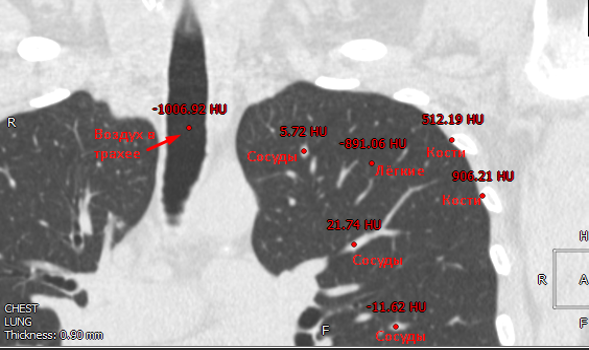

Шкала Хаунсфилда — количественная шкала рентгеновской плотности, которая измеряется в единицах Хаунсфилда, обозначаемых HU.

Рентгеновская плотность вычисляется на основе коэффициента ослабления вещества, то есть степени уменьшения мощности излучения при прохождении через это вещество.

Рентгеновская плотность вычисляется по формуле:

$$display$${μ_{X}-μ_{water} over μ_{water}-μ_{air}} times 1000$$display$$

где — линейные коэффициенты ослабления для измеряемого вещества, воды и воздуха.

Рентгеновская плотность бывает отрицательной, потому что нулевая рентгеновская плотность соответствует воде. А значит все вещества, через которые рентгеновские волны проходят с меньшим уменьшением мощности излучения, чем через воду (например, легочные ткани, воздух), будут иметь отрицательную рентгеновскую плотность.

Ниже перечислены приблизительные рентгеновские плотности для различных тканей:

С помощью томографа получены данные о рентгеновской плотности в каждой точке пространства. Воксели воздуха имеют рентгеновскую плотность в промежутке от -1100 до -900 HU, а воксели дыхательных органов от -900 до -300 HU. Поэтому можем убрать все лишние воксели, имеющие рентгеновскую плотность больше -300 HU. В итоге получим бинаризованный воксельный объём, содержащий только дыхательные органы и воздух.